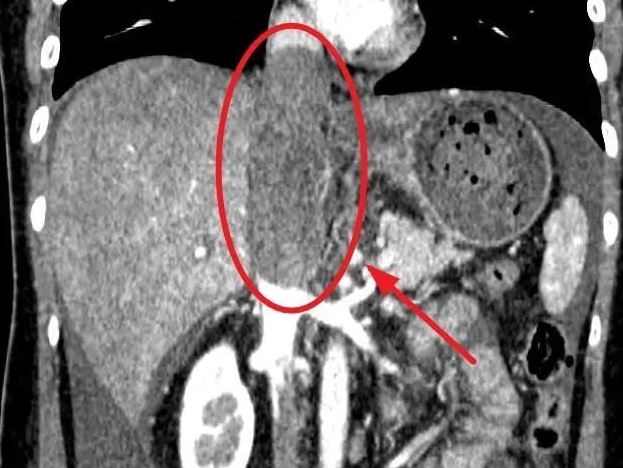

2022年影像学检查显示,刘芳霞体内肿瘤已侵入主要血管

这种肿瘤极为罕见,且侵入了关键血管,此时直径已有9.2厘米,手术难度和风险极高,若要在上级医院手术治疗,需排队等待 4 个多月。